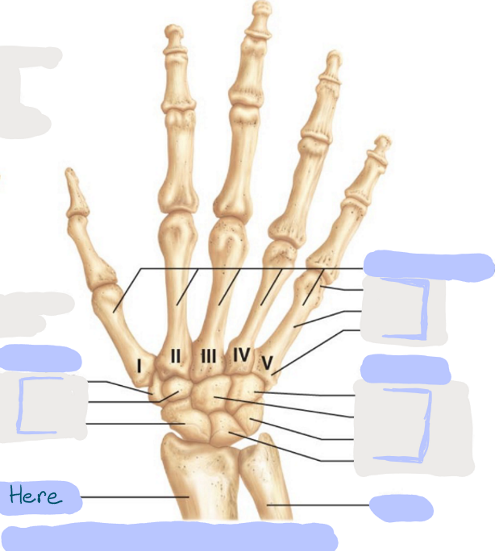

What is this picture of?

Anterior View of the Right Hand

What is here?

Where is the Ulna?

What is here?

Where is the Radius?

What is here?

Where are some of the Carpals?

What is here?

Where are some of the Carpals?

What is here?

Where are the Phalanges?